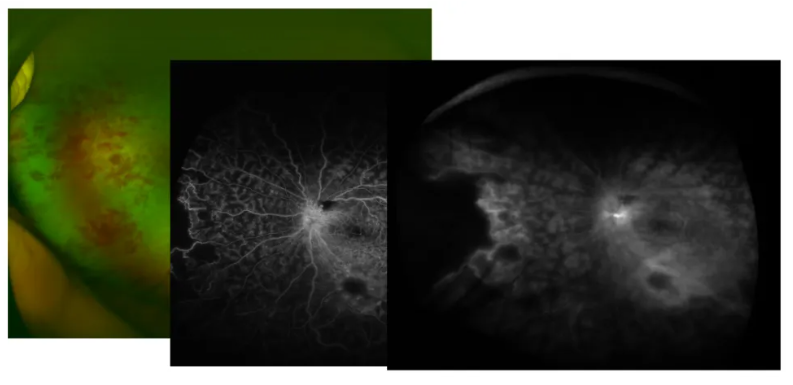

根据眼底FFA检查结果:ⅡA期1例,ⅡB期10例,ⅢB期1例。

影像学特征显示:所有患儿均出现黄白色视网膜下渗出伴动脉瘤样改变,10例(83.33%)存在黄斑区浓密硬性渗出,1例表现为广泛视网膜脱离,1例可见黄斑前牵拉膜。

FFA检查发现:6例患儿存在毛细血管扩张且范围超过3个象限,另各有3例患儿的毛细血管扩张范围为1个象限和2个象限;所有患儿的异常毛细血管及无灌注区均位于颞侧、颞上或颞下周边视网膜;对侧眼周边视网膜亦发现血管异常。

诊断:左眼Coats病,左眼渗出性视网膜脱离ⅢA期